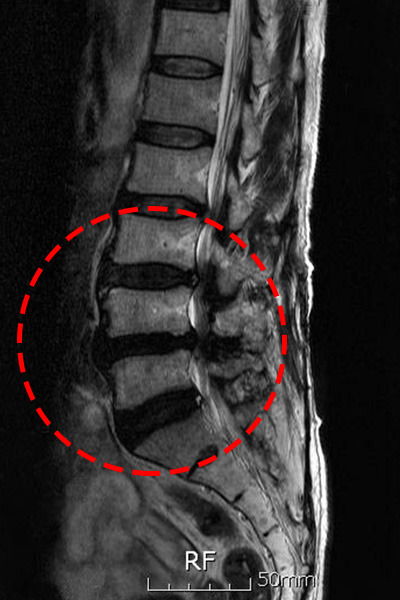

척추관 협착증(허리협착증)은 척추 신경이 지나가는 통로가 좁아지면서 통증, 저림, 보행 장애가 나타나는 질환입니다. 특히 50대 이후 급격히 증가하며, 조기 진단과 관리가 매우 중요합니다.

🩹 단계별 허리 협착증 증상

- 초기 — 허리 뻐근함, 다리 저림

- 중기 — 오래 걷기 어려움, 계단 통증

- 후기 — 다리 근력 약화, 보행 장애